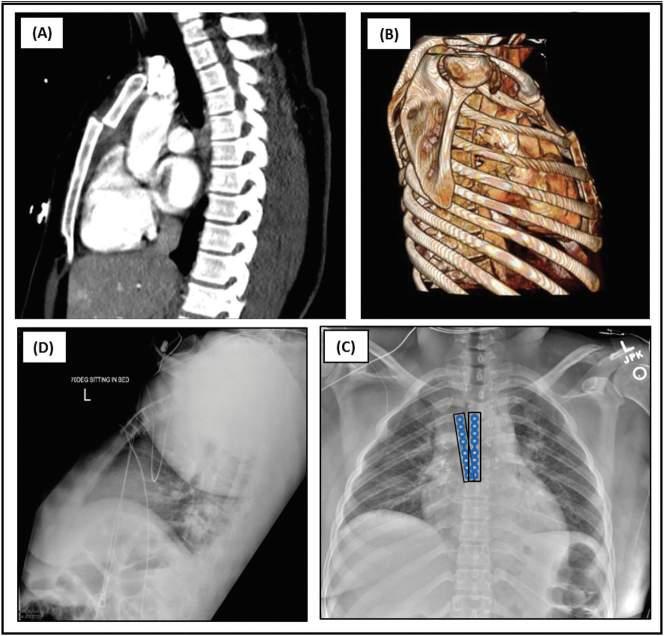

Fig.1.11 Crushinjuryofthechestwithmassivechestwalltrauma.(A)Computedtomographic(CT) three-dimensionalreconstructionimageofthechestwallonadmission.(B)CTimageofthesternum.(C) Surgicalprocedure:fixationofsternalandmultiplecostalcartilagefractures.(D)CTthree-dimensional reconstructionimageofthechestwallafteroperation.(E)Chestfilmobtained4daysafteroperation. (FromGaoE,LiY,ZhaoT,etal.Simultaneoussurgicaltreatmentofsternumandcostalcartilagefractures. AnnThoracSurg.2019;107(2):e119 e120[Fig.1].ISSN0003-4975, https://doi.org/10.1016/j. athoracsur.2018.06.044, http://www.sciencedirect.com/science/article/pii/S0003497518310488.)

DIFFERENTIALDIAGNOSIS

Asmentioned,thepainofcostosternals yndromeisoftenmistakenforpainof cardiacorigin,anditleadstovisitsto theemergencydepartmentandunnecessarycardiacworkups.Iftraumahasoccurred,costosternalsyndromemay coexistwithfracturedribsorfracturesofthesternumitself,whichcanbe missedonplainradiographsandmayrequireCTorradionuclidebonescanningforproperidentification( Fig.1.11 ).Tietzesyndrome,whichispainful enlargementoftheuppercostochondral cartilageassociatedwithviralinfection,maybeconfusedwithcostosternalsyndrome( Box1.1 ).